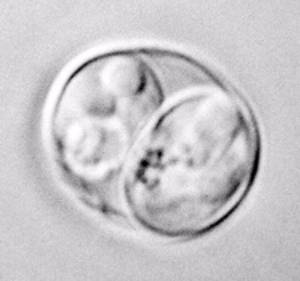

Neosporosis is caused by infection with the protozoa Neospora caninum. Neosporahas been found world-wide and in many species other than cattle. Currently abortion due to Neospora has been shown in cattle, sheep and horses. The dog and other canids (such as foxes) are the definitive host. That is they are the animals in which the parasite becomes sexually mature and reproduces.

- Identification of parasite in the calf tissue